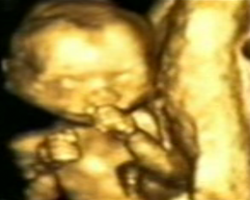

- ecografia fetală 4D ne prezinta imaginea corpului fătului aflat în uter cu mişcările pe care le are în momentul examinării.

Pentru a vedea pozele marite puneti mouse-ul in interiorul pozelor mici: